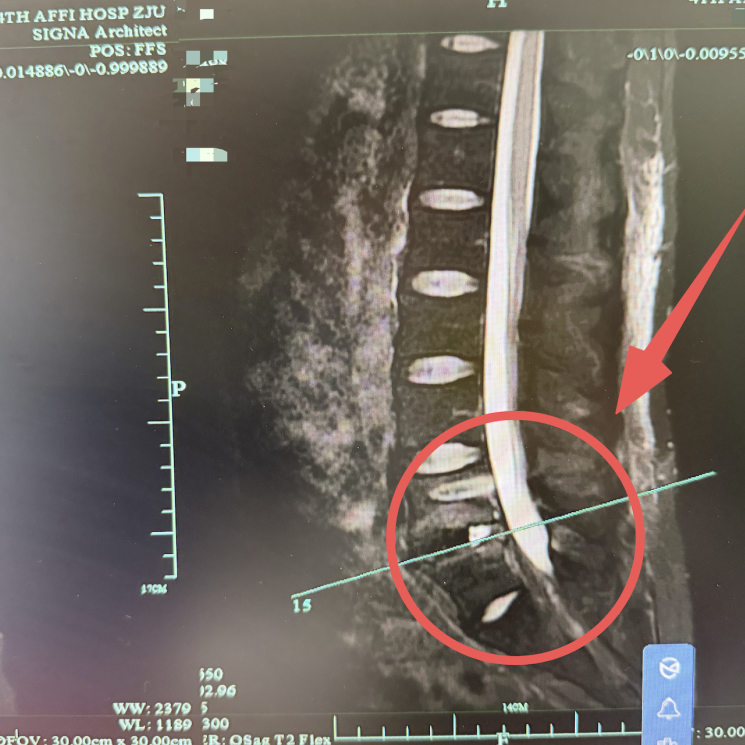

接诊后,马建军首先为孙先生完善了各项检查,结合他的病史和症状,明确诊断为严重腰椎间盘突出合并终板炎,且因病情复发、神经长期受压,已经出现了明显的神经损伤。

「孙先生存在巨大的腰椎间盘突出,压迫神经,同时合并了明显的终板炎,两者叠加,比单一病症凶险得多,严重时会导致下肢无力、大小便障碍,甚至瘫痪。」

马建军副院长解释道,孙先生之前在某大医院做过腰椎孔镜手术,目前属于突然复发,手术翻修难度明显增大,若采用传统开放手术,存在创伤大、出血多、恢复慢等等问题,还容易加重组织粘连。结合他的年龄和工作需求,团队决定为他采用量身定制的腰椎改良双孔微创融合技术,这也是马建军的核心优势之一。